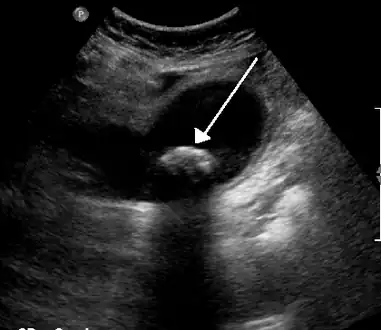

Diagnosis is typically confirmed by abdominal ultrasound. Other imaging techniques used are ERCP and MRCP. Gallstone complications may be detected on blood tests.[2]

On abdominal ultrasound, sinking gallstones usually have posterior acoustic shadowing. In floating gallstones, reverberation echoes (or comet-tail artifact) is seen instead in a clinical condition called adenomyomatosis. Another sign is wall-echo-shadow (WES) triad (or double-arc shadow) which is also characteristic of gallstones.[37]